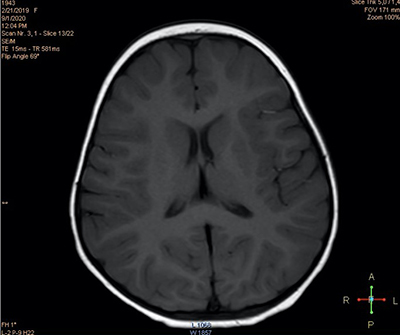

При проведении нейровизуализационного исследования (МРТ 2 Тл) выявлены признаки некоторого усиления МР-сигнала в парагиппокампальной области (см. рис. 2а) и незначительного расширения переднего субарахноидального пространства (см. рис. 2б), что может свидетельствовать в пользу перенесенной гипоксически-ишемической перинатальной энцефалопат На третьи сутки количество эпизодов отведения глаз сократилось до 6, при этом их продолжительность не превышала нескольких секунд.

Рисунок 2а. МРТ-исследование. Признаки усиления МР-сигнала в парагиппокампальной области.

Рисунок 2б. МРТ-исследование. Признаки незначительного расширения переднего субарахноидального пространства.На четвертые сутки количество пароксизмов продолжило уменьшаться и составило всего 2 эпизода длительностью 1–2 секунды. При этом ранее сопутствовавших данным состояниям нарушений координации не отмечалось.

Инструментально-диагностические и лабораторные исследования чаще всего демонстрируют нормальные показатели нейровизуализации, электроэнцефалографии и метаболических параметров крови и ликвора у детей с идиопатическими (генетическими) формами заболевания. Золотой стандарт нейровизуализационного обследования — МРТ головного мозга, как правило, не выявляет патологических изменений.